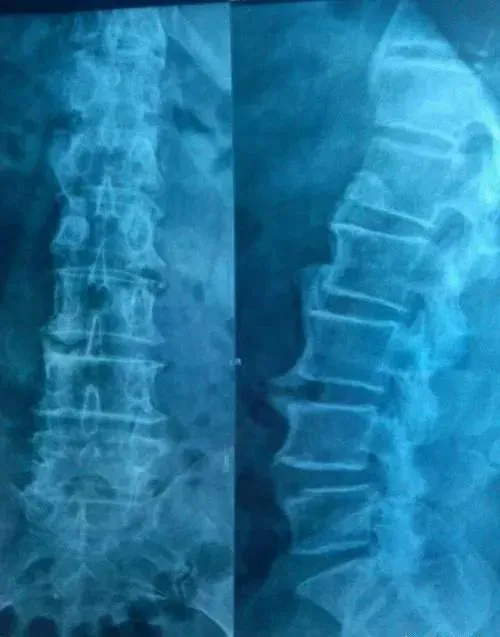

椎间盘突出与骨质增生有什么区别?

腰痛是许多人面临的问题,但你可能不知道,导致腰痛的原因可能大不相同。椎间盘突出和骨质增生就是两种常见的脊柱问题,它们虽然都可能导致腰痛,但实际上是两种完全不同的疾病。

椎间盘突出,顾名思义,是指脊柱椎骨之间的椎间盘发生问题。正常情况下,椎间盘像一个弹性垫子,保护脊柱并吸收冲击。但当椎间盘的外层破裂,内部的髓核突出时,就会压迫周围的神经,引起疼痛。这种疾病多见于年轻人和中年人,尤其是那些长期保持不良姿势或从事重体力劳动的人。

相比之下,骨质增生,也被称为骨刺,是一种与年龄相关的退行性变化。它通常发生在关节处,是身体为了应对关节损伤或劳损而产生的一种自我修复机制。骨质增生多见于老年人,是由于长期的关节磨损、钙质流失等因素导致的。